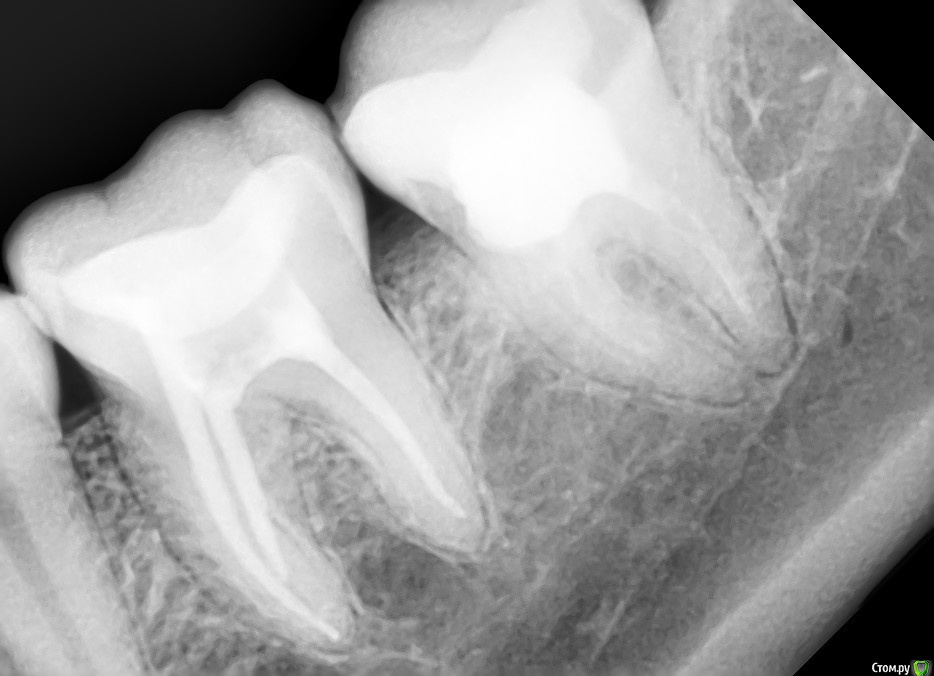

DA89 Опубликовано 8 мая, 2015 Поделиться Опубликовано 8 мая, 2015 Добрый деньПолгода назад была перелечена 7 снизу (был найден доп канал), положили кальций на 2 нед, неприятные ощущения прошли, запломбировали гутаперчей. Через 3 нед вновь появились неприятные ощущения (боль в ухе, подчелюстной лимфоузел увеличен и ощущения как будто зуб чешется, после того как пожую на него становится легче). Пропила курс настойки эхинацеи, стало легче, потом снова все вернулось. На сегодняшний день периодически боль в ухе, челюстном суставе, зуб как будто чешется, хочется на него накусить и увеличивается лимфоузел. Может дня 3 вообще ничего не беспокоить, либо беспокоить мин 30 в день и проходит, а может и весь день беспокоить. Доктор который его лечил сказал удалять. Есть ли смысл снова перелечивать каналы? Прикрепила снимки до лечения и спустя полгода Ссылка на комментарий

DA89 Опубликовано 14 мая, 2015 Автор Поделиться Опубликовано 14 мая, 2015 значит не совсем правильно чистите это косвенно говорит о наличии пародонтальной проблемы в этой области то есть болит без 3х недель полгода?да, уже полгода, судя по снимку, появились ли изменения за это время?Лечащий доктор сказал если чешется зуб и десна, это говорит об инфекции в корне...Другой стоматолог сказала что справиться с хроническим периодонтитом поможет лазерная физиотерапия. Есть ли смысл или это просто выкачивание денег? Ссылка на комментарий

Гарриевич Опубликовано 15 мая, 2015 Поделиться Опубликовано 15 мая, 2015 Другой стоматолог сказала что справиться с хроническим периодонтитом поможет лазерная физиотерапия не является лечебным мероприятием Лечащий доктор сказал если чешется зуб и десна, это говорит об инфекции в корне... не согласен появились ли изменения за это время? изменений не вижу, по снимку все в порядке зуб как будто чешется хочется на него накусить после того как пожую на него становится легче все это говорит за связочный аппарат, ищите проблему там Ссылка на комментарий